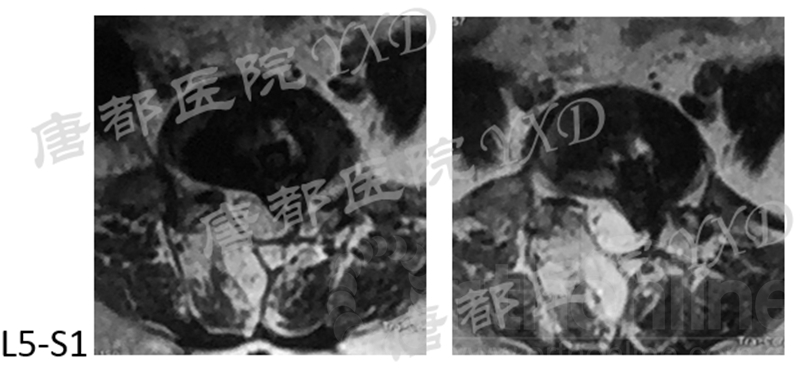

影像学检查:

诊断:腰椎间盘突出症术后复发

手术方案:显微镜辅助MI-TLIF腰椎翻修术